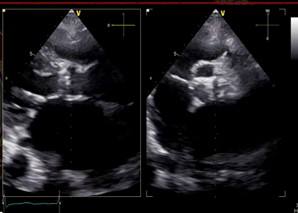

Relevant Test Results Prior to Catheterization

Initial ECG revealed AF. Transthoracic echocardiography revealed concentric LVH with a 70 % of left ventricular systolic function, normal right ventricular systolic function, bi-atrial enlargement and severe calcific aortic stenosis which classified as stage D1 (AVA 0.98 cm2 by AV VTI, AV Vmax 4.03 m/s, mean AV pressure gradient 38.21 mmHg). Following as the Heart Team discussion, Transcatheter Aortic Replacement (TAVR) following coronary angiography (CAG) was scheduled as the optimal choice.

Under local anesthesia and conscious sedation, femoral arteries (FA) were accessed by 8-Fr sheath at right FA and two of 8-Fr sheaths at left FA for pigtail catheter and snare-assisted device. Aortography was conducted by pigtail catheter to locate aortic cusp. An Amplatz left catheter over a 0.035-inchJ-tip wire was placed at aortic cusp via the RFA which was then exchanged with an Amplatz Super Stiff wire to upsized 16-Fr Braidin sheath. The aortic valve was crossed with an Amplatz left catheter over a straight-tip wire under cuspoverlap views (LAO16, CAU 30), peak-to-peak gradient of 19 mmHg. During RV pacing, a Safari Extra Small guidewirewas positioned in LV and the AV was pre-dilated by an 18 × 40 mm Alwide balloon. Subsequently, a 27 mm VitaFlow valve was deployed in an optimal position under snare-assisted. Post-deployment aortography revealed mild AR, LVEDP of20 mmHg, and 4 mmHg of LVOT gradient. Post-dilation was performed by a 24 × 40mm VACC III balloon. The FA was closed by 6-Fr Proglide at the right and 8-Fr AngioSeal at the left. Post-TAVR TEE showed mild PVL without significant transvalvular gradient and preserved LVEF of 64%. One-month after the TAVR, she was diagnosed with early-stage colonic cancer. A laparoscopic hemicolectomy which completed pre-operative evaluation, coronary revascularization, TAVR and appropriated medication was performed as time-sensitive surgery following by CMT with curative intent.